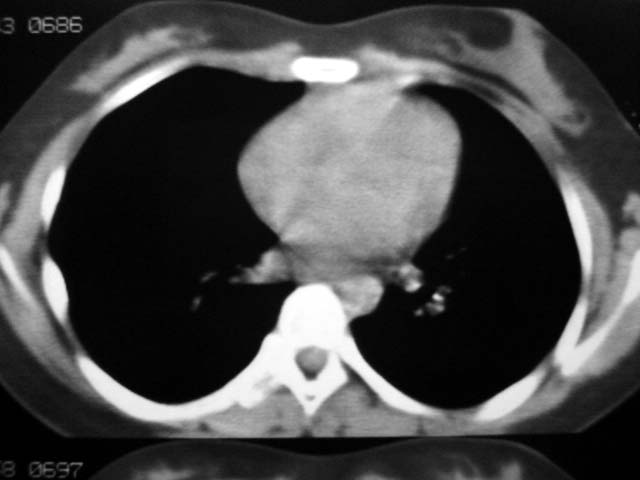

标题: CT12463:女,19岁,炎性假瘤?结核球? [打印本页]

女,19岁,体检时发现。炎性假瘤?结核球?

早产儿,幼时体弱,常感冒肺部感染,13岁后好转。两月前“感冒”后咳嗽两周。

纵隔窗肿块明显较肺窗小,切粗长毛刺,“倒核桃”征:考虑炎性假瘤

考虑炎症,抗炎后复查。理由:病变肺窗显示的大小明显大于纵隔窗,提示病变周围为密度偏低的渗出改变。不同于结核球和肿瘤。